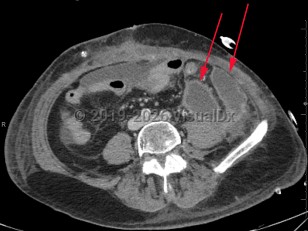

Intraabdominal abscessIntraabdominal abscess